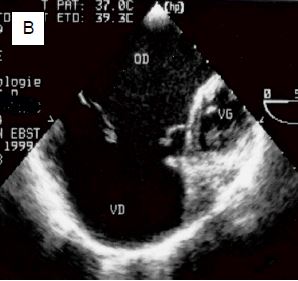

Figure 14.46 : Hypoplasie ventriculaire. A : hypoplasie du VD avec atrésie tricuspidienne ; le VD apparaît comme une chambre accessoire antérieure reliée au ventricule unique (VU) anatomiquement gauche par une CIV; il n’y a pas de communication entre l’OD et le VD, mais une CIA entre les deux oreillettes. B : hypoplasie du coeur gauche ; le VG est une petite chambre accessoire postérieure, l’aorte ascendante est hypotrophique; le VU est anatomiquement le VD, connecté à la valve tricuspide et à l’OD. L’OD reçoit le sang systémique par les veines caves, et le sang veineux pulmonaire par une CIA.

Cette dénomination recouvre un ensemble de pathologies qui sont plus ou moins l’inverse de la précédente : le VG est petit et non-fonctionnel, un degré variable d’hypoplasie ou une atrésie franche caractérise la valve mitrale, la valve aortique, l’aorte ascendante et la crosse; cette dernière peut même être interrompue. Les retours veineux systémique et pulmonaire se mêlent dans l’OD ; le VD alimente la circulation pulmonaire et la circulation systémique par l’intermédiaire du canal artériel (Figure 14.46B). Dès que le débit de ce dernier diminue, le flux systémique s’effondre et le bébé décède en 3-5 jours.

Figure 14.46B : Hypoplasie du coeur gauche ; le VG est une petite chambre accessoire postérieure, l’aorte ascendante est hypotrophique; le VU est anatomiquement le VD, connecté à la valve tricuspide et à l’OD. L’OD reçoit le sang systémique par les veines caves, et le sang veineux pulmonaire par une CIA.